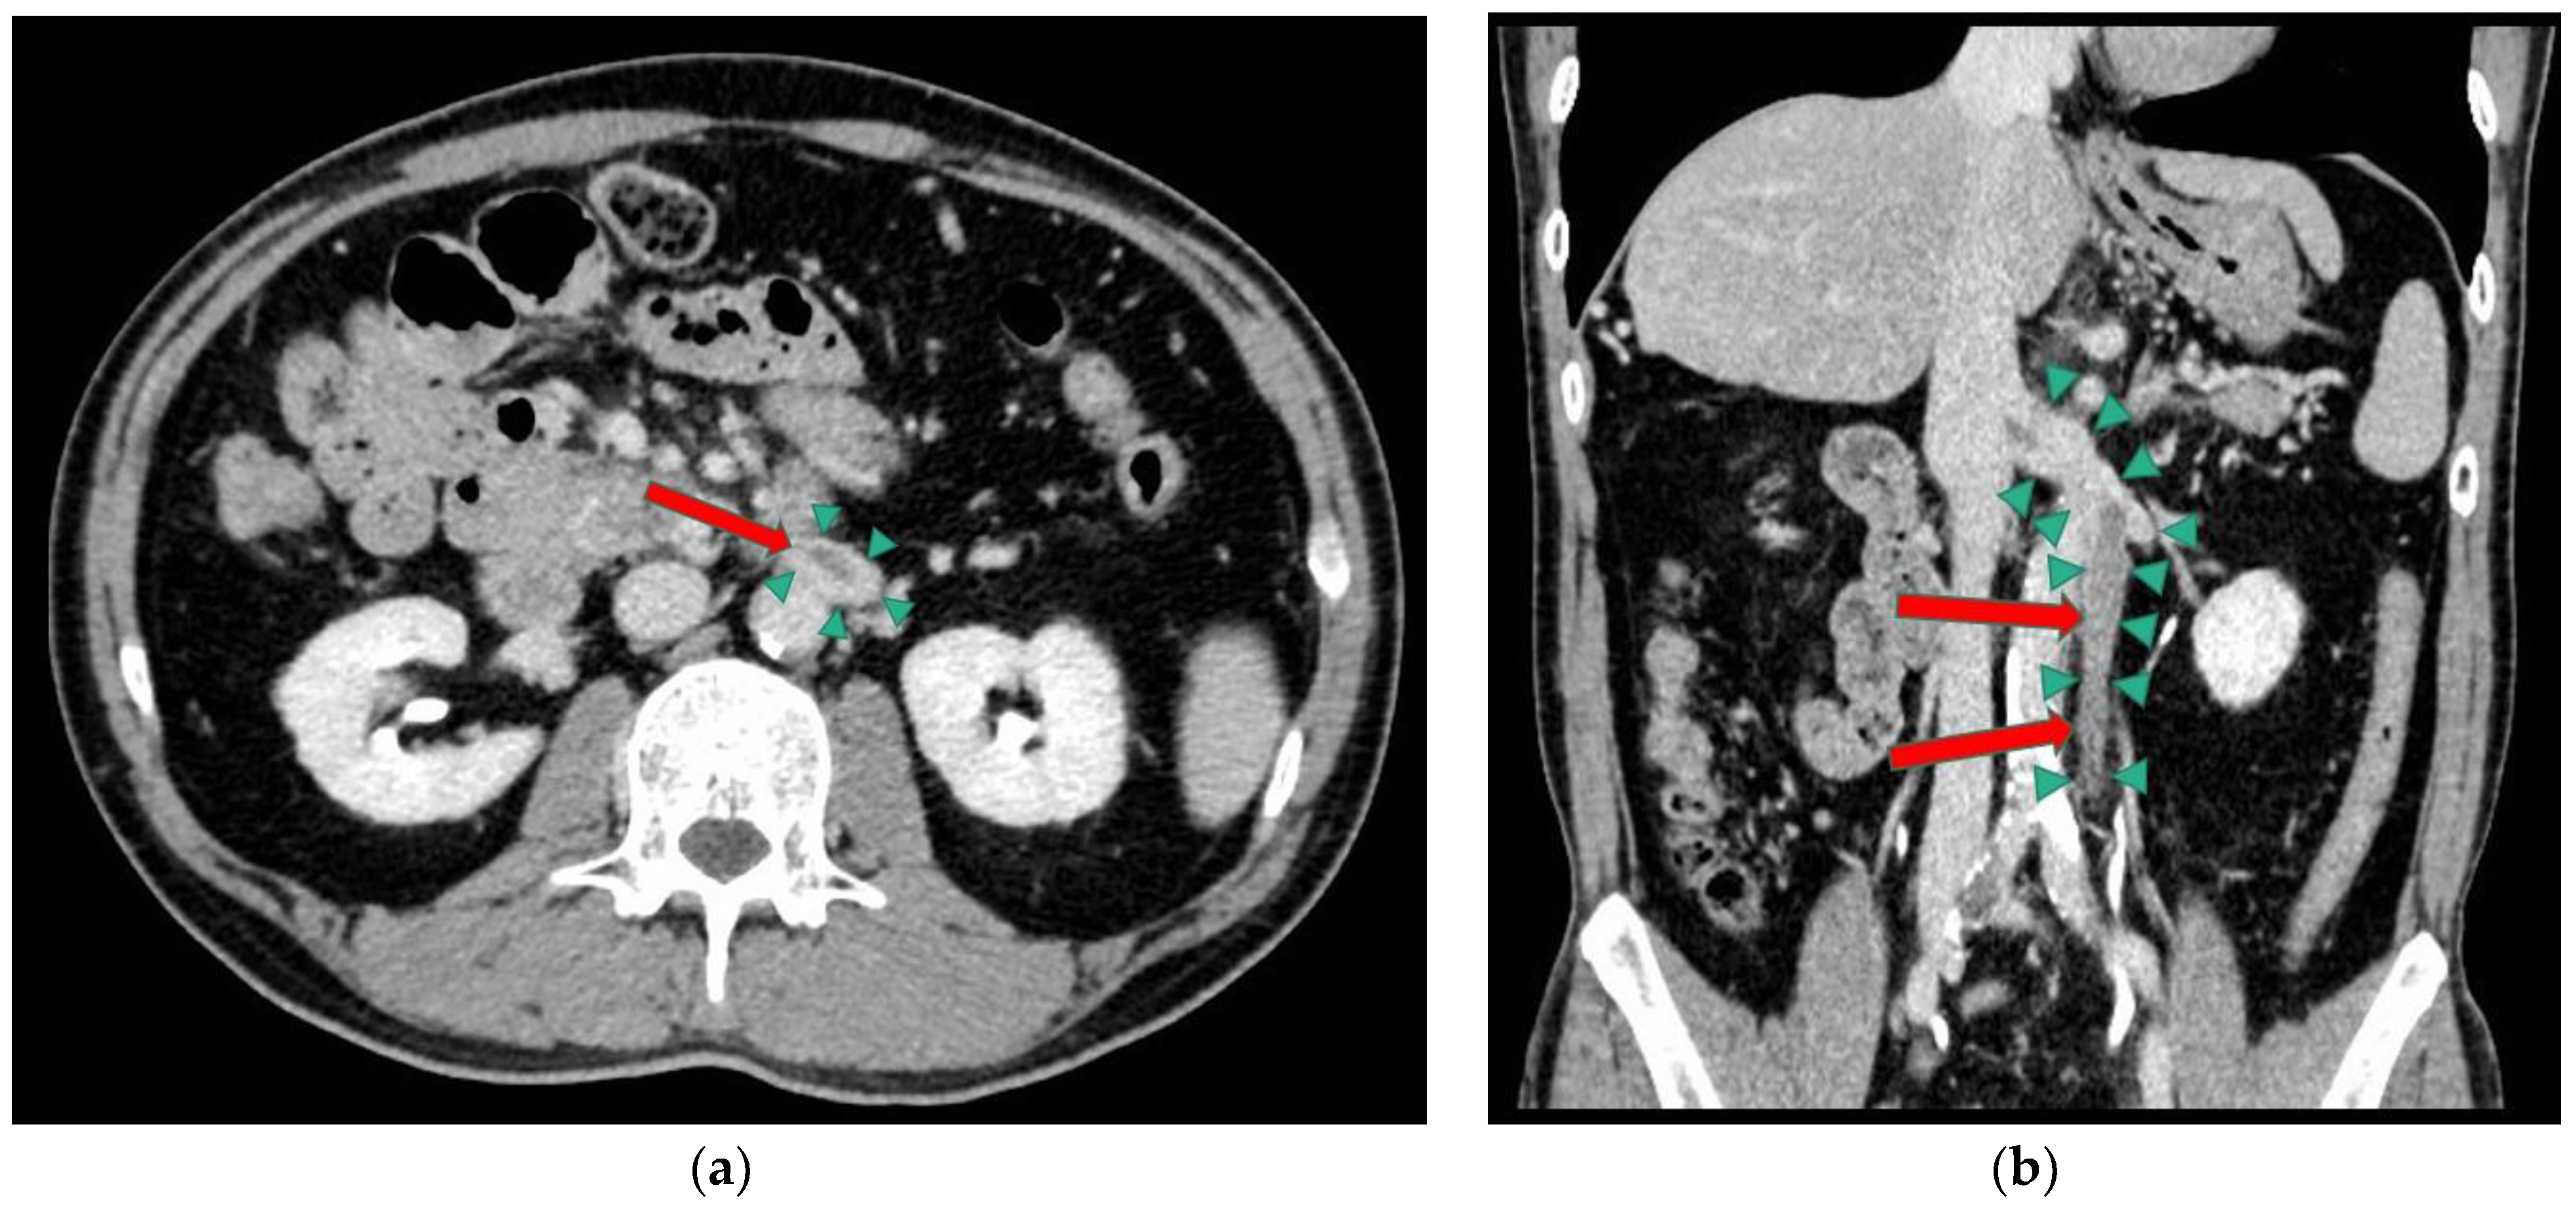

On the 12-lead ECG, heart rate of 98 beats/min, sinus rhythm, a positive axis, clear Q waves, and negative T waves during induction III were observed. Chest radiography (Figure 1) demonstrated slightly increased permeability in the bilateral middle lung fields. In transthoracic echocardiography (Figure 2), both left and right ventricles were of normal in size, as seen on the parasternal left border long-axis tomogram and parasternal left border short-axis tomogram, with no evidence of left ventricular compression. In the four-chamber view, the right ventricle seemed to be slightly enlarged. The tricuspid valve systolic pressure gradient was 22.5 mmHg. Chest contrast-enhanced CT revealed thrombi in the bilateral main pulmonary arteries (Figure 3). Abdominal contrast-enhanced CT revealed thrombi in the IVC duplication, left common iliac vein, left IVC, and left renal vein (Figure 4). The left IVC was slightly smaller in diameter than the normal IVC (right IVC). It branched from the left renal vein and descended alongside the left kidney to contact the left common iliac vein. A tributary branch to the right IVC was observed immediately before it joined the left common iliac vein. The left femoral vein similarly demonstrated a few low-absorption areas, suggestive of thrombi.

Figure 4. Abdominal contrast-enhanced computed tomography scan. Thrombi in the duplication of the inferior vena cava (IVC), left common iliac vein, left IVC, and left renal vein. (a) Axial view. (b) Coronal view. Medicina 59 00605 i002 thrombus. Medicina 59 00605 i003 duplication of the IVC.